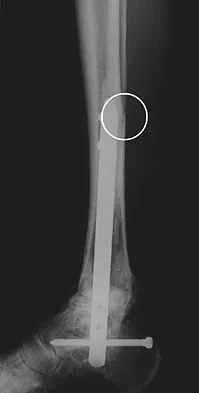

A 42-year-old man sustained the periprosthetic fracture shown in Figures 19a and 19b. The femoral component is well fixed. What is the next most appropriate step in management?

Explanation

The patient has a periprosthetic fracture below the femoral stem. The component is porous coated and well fixed. Open reduction and internal fixation, leaving the stem in place, can be performed when bone quality is good. Plating with or without allograft struts and supplemental cerclage fixation generally is acceptable. If the component is loose, revision to a longer device is recommended with appropriate stabilization of the fracture using the aforementioned methods. If bone loss has occurred, allograft supplementation or a tumor prosthesis may be indicated. Fractures located well below the stem tip can be treated without regard for the prosthesis. Closed reduction and bracing is not associated with good results for periprosthetic femoral fractures. Retrograde intramedullary nailing is not appropriate for this fracture. Duncan CP, Masri BA: Fractures of the femur after hip replacement. Instr Course Lect 1995;44:293-304.